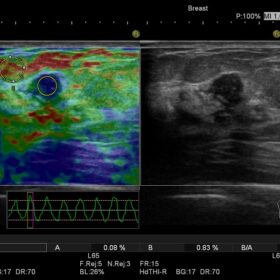

- Hitachi Real-time Tissue Elastography (HI-RTE)

Hitachi EUP-L53L Breast Linear

Hitachi EUP-L54MA Breast Linear

Hitachi EUP-74M Breast Linear